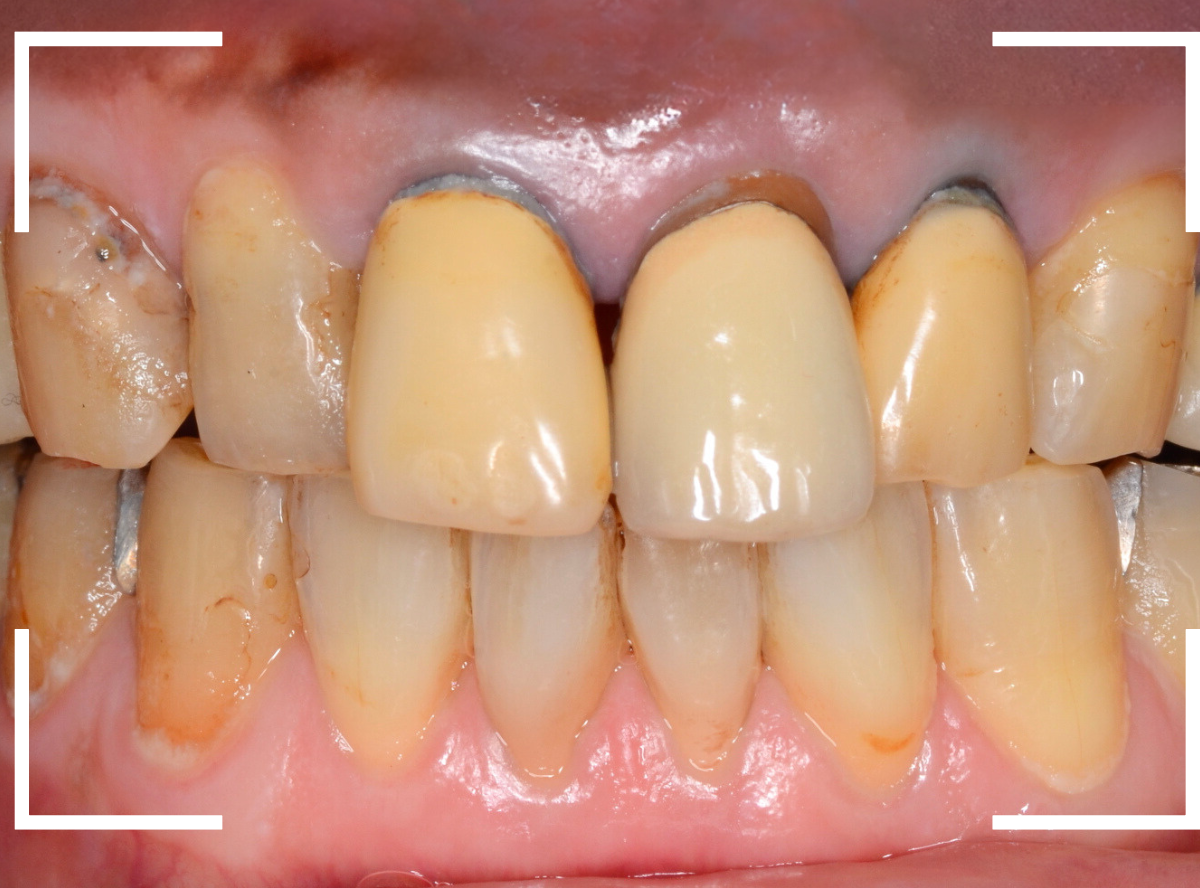

今回は、前歯のさし歯が古くなったので、セラミックで綺麗にしたいというご希望の患者さんです。

患者さんのご希望は白い〇部分の3本でしたが、レントゲン検査をすると隣の2本も虫歯があり、一緒に治療をする事になりました。

左側の2本は虫歯を除去してみないと最終的にどのようにお治しするか何とも言えない状況でしたので、同時に治療しながら最終的な仕上げはご相談、となりました。

まず、前歯のさし歯を外します。

神経を取っている歯(無髄歯)ですので、痛みはありませんが、前後の2本は虫歯になっています。

これら、歯全体を覆うさし歯の中の虫歯はレントゲン写真でも写ってこないため、治療前に正確な判断ができません。